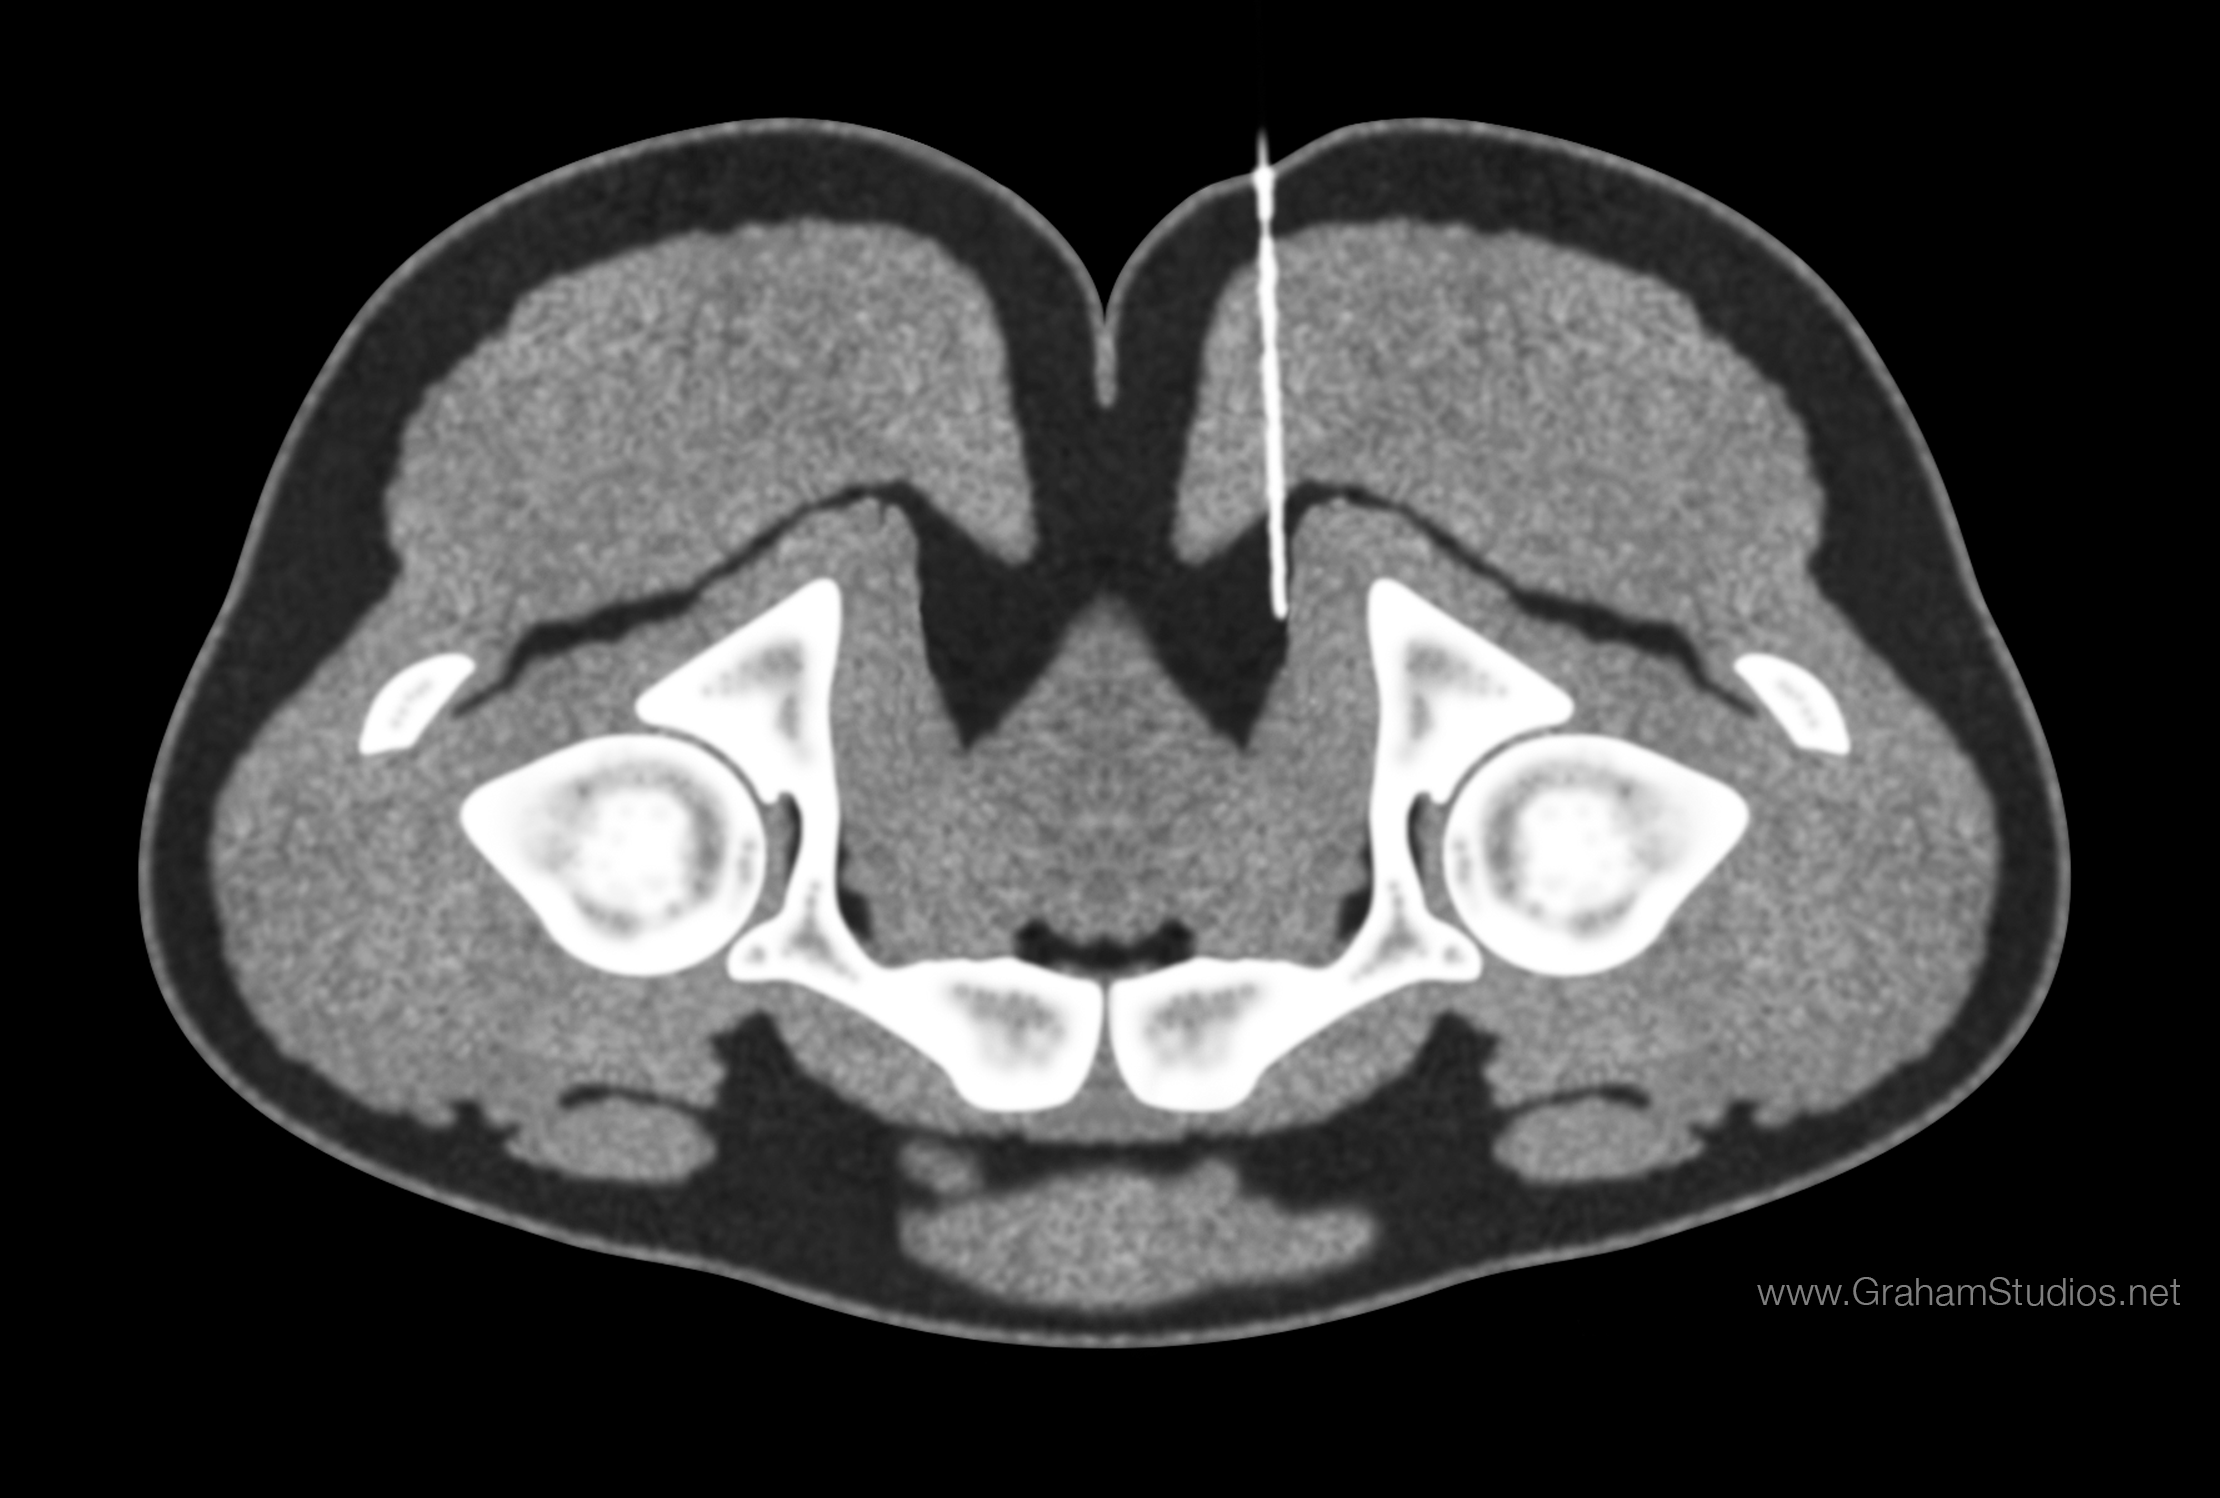

음부신경은 일반적인 CT 또는 MRI에서 촬영하기는 어렵지만, CT 유도 하에 음부 신경혈관다발 근처에 바늘을 놓을 수 있다. 궁둥뼈가시는 CT에서 쉽게 식별할 수 있는 구조이기 때문에, 주로 이 높이에서 주사가 이루어진다. 척수마취용침(스파이날 니들)은 볼기의 근육을 통해 궁둥뼈가시의 몇 밀리미터 내에 주사한다. 그런 다음 조영제(X선 염료)를 주입하여 음부신경관 안의 음부신경을 잘 보이게 하고 바늘이 올바르게 들어갔는지 확인할 수 있다. 이후 신경에 코르티손과 국소 마취제를 주입하여 외부 생식기의 만성 통증(여성의 경우 외음부통증), 골반 및 항문과 곧창자의 통증을 확인하고 치료할 수 있다.[48][49]

음부신경은 일반적인 CT 또는 MRI에서 촬영하기는 어렵지만, CT 유도 하에 음부 신경혈관다발 근처에 바늘을 놓을 수 있다. CT에서 쉽게 식별할 수 있는 구조인 궁둥뼈가시 높이에서 주로 주사한다. 척수마취용침(스파이날 니들)은 볼기의 근육을 통해 궁둥뼈가시의 몇 밀리미터 내에서 주사한다. 그런 다음 조영제(X선 염료)를 주입하여 음부신경관 안의 음부신경이 잘 보이게 하고 바늘이 올바르게 들어갔는지 확인할 수 있다. 그런 다음 신경에 코르티손과 국소 마취제를 주입하여 외부 생식기의 만성 통증(여성의 경우 외음부통증), 골반 및 항문과 곧창자의 통증을 확인하고 치료할 수 있다.[48][49]4. 4. 신경 잠복기 검사